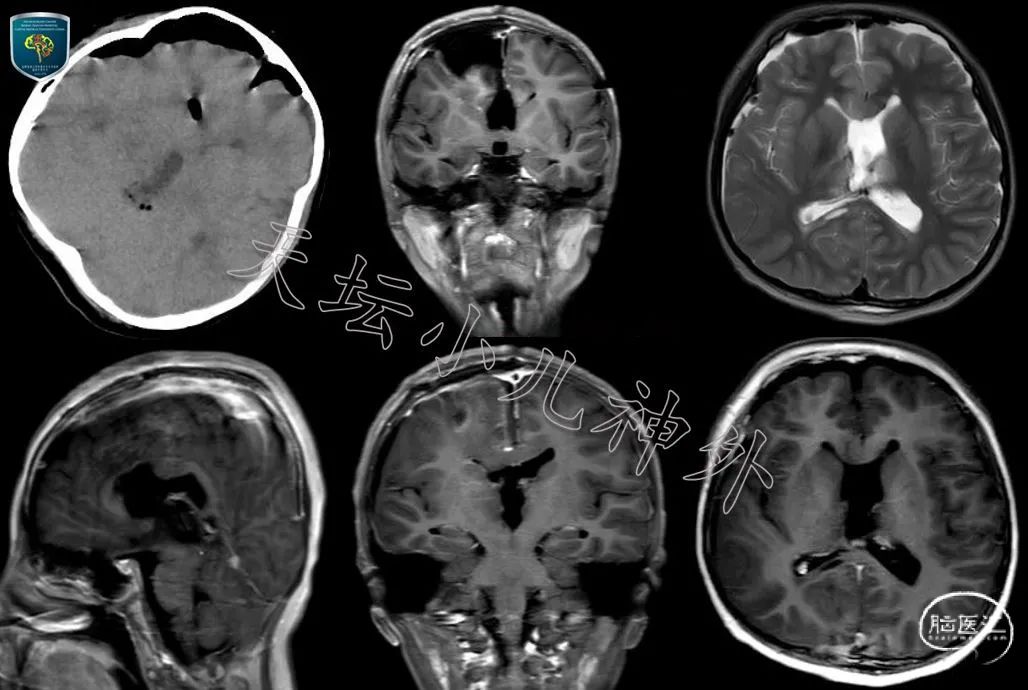

图2 随访四年,患儿出现头晕、头胀症状,复查头部CT/MRI显示,钙化灶明显增大,向松果体区突入,不均匀强化,我院影像报告提示:畸胎瘤?松果体母细胞瘤?